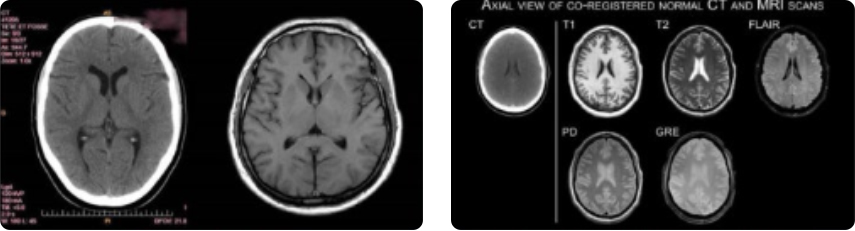

CT와 MRI

방사선을 이용하는 CT와 자기장을 이용하는 MRI는 원리가 다르므로 각각 볼 수 있는 질환에 차이가 있어 외상이나 뇌출혈이 의심될 때에는 CT를 통해 빠른 진단을 하고 어지럼증, 두통, 치매, 뇌경색 등 뇌혈관질환이 의심되는 경우 고해상도 MRI 검사를 진행하는 것이 좋습니다.

방사선을 이용하는 CT와 자기장을 이용하는 MRI는 원리가 다르므로 각각 볼 수 있는 질환에 차이가 있습니다.

CT는 방사선을 이용하여 촬영하기 때문에 비교적 단시간에 촬영이 가능하여 골절이나 외의 출혈 여부를 잘 확인할 수 있다는 장점이 있습니다. 그러나 CT는 뇌의 백질변성, 소혈관질환, 작은 크기의 병변은 확인이 어렵고 MRI보다 해상도가 낮아 CT에서는 발견이 되지 않았는데 MRI에서는 발견되는 병변들이 있습니다.

따라서 외상이나 뇌출혈이 의심될 때는 CT를 통해 빠른 진단을 하고 어지럼증, 두통, 치매, 뇌경색 등 뇌혈관 질환이 의심되는 경우에는 고해상도 MRI 검사를 진행하는 것이 좋습니다.